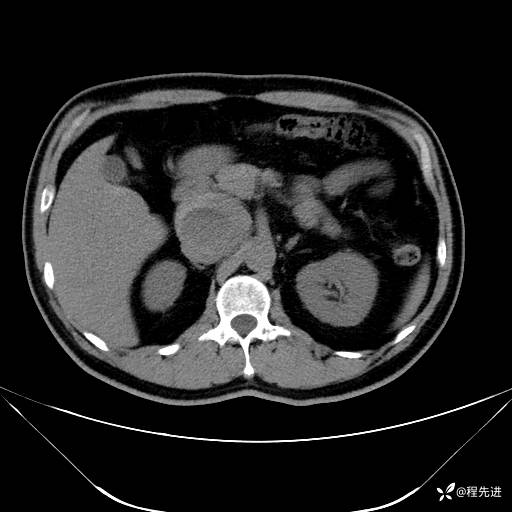

【腹盆】特别精彩病例|发现腹膜后肿物1月余

主诉:发现腹膜后肿物1月余

现病史:患者1月余前查体,行超声检查提示:后腹膜囊实性肿块;慢性胆囊炎伴胆囊内结石;无腹痛腹胀,不伴腹泻发热等;偶感腰背部酸痛。

CT平扫+增强: